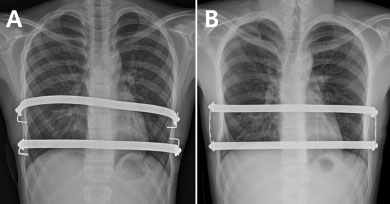

정진용 교수팀은 기존 2개의 교정 막대를 개별적으로 고정하는 ‘분리고정 수술법’(사진A)과, 각 교정 막대 양 끝을 작은 금속 막대로 연결해 사각형 형태로 고정하는 ‘사각고정 수술법’(사진B)의 결과를 비교 분석했다.

정 교수팀은 2011년 9월부터 2016년 1월까지 2개의 금속막대를 삽입한 너스수술 환자 86명을 교정 막대의 양쪽 측면을 각각 고정한 A군(44명, 사진A)과 각 교정 막대를 세로형 막대와 연결해 사각형 형태로 고정 시킨 B군(42명, 사진B)으로 나눴다.